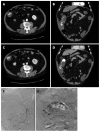

Figures